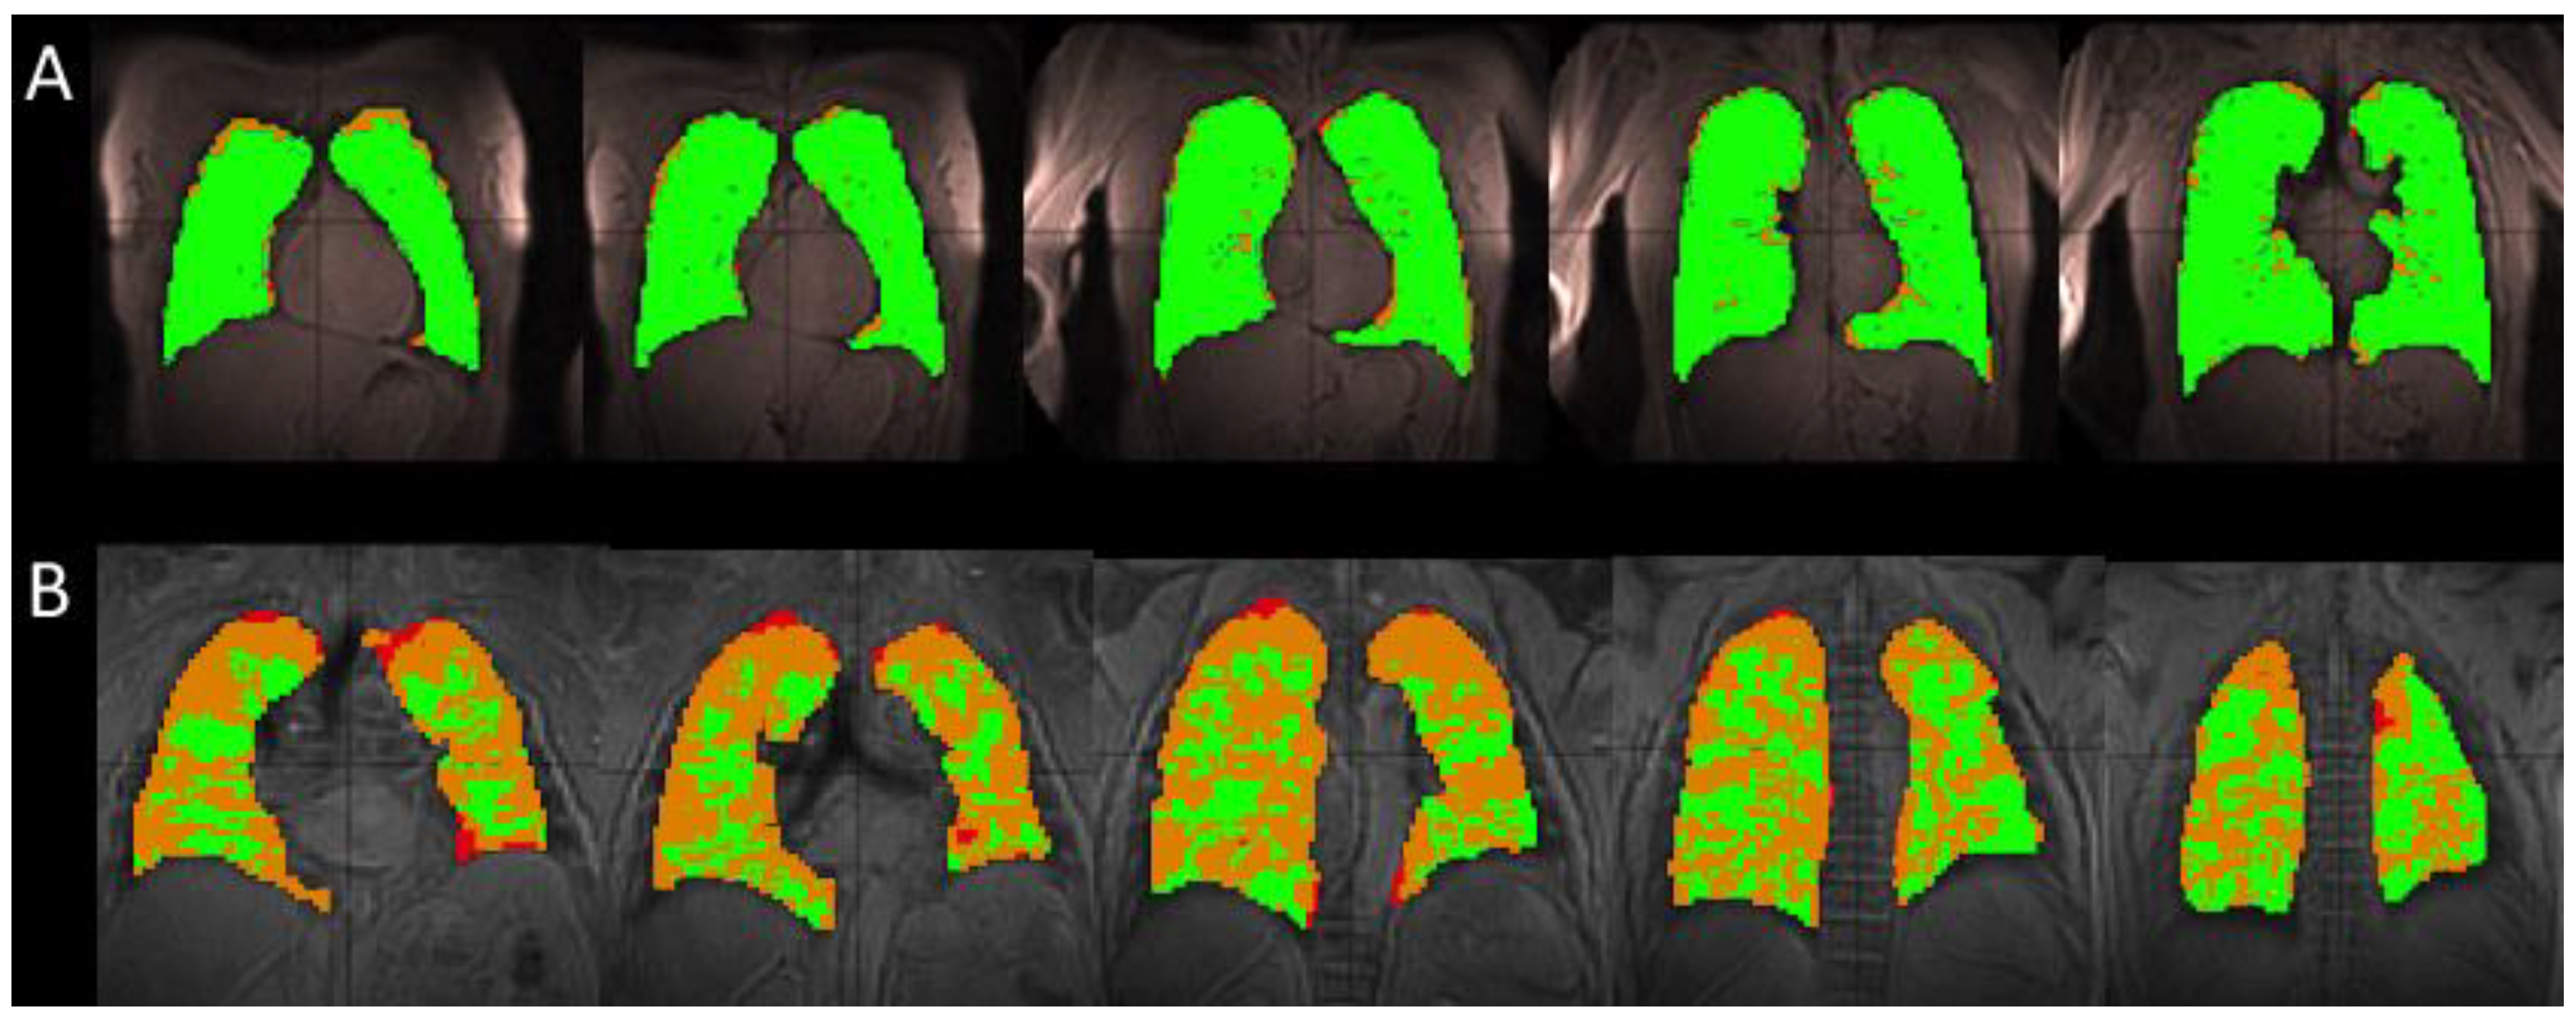

3.1. Comparison of Healthy and IPF Ventilation Images

3.2. Comparing Ratio Maps between Healthy and IPF

| Ventilation | Total Volume [L] | 4.1 ± 0.56 | 2.6 ± 0.70 | <0.05 |

| Relative Defect Volume [%] | 9.6 ± 7.37 | 34.1 ± 6.44 | <0.05 | |